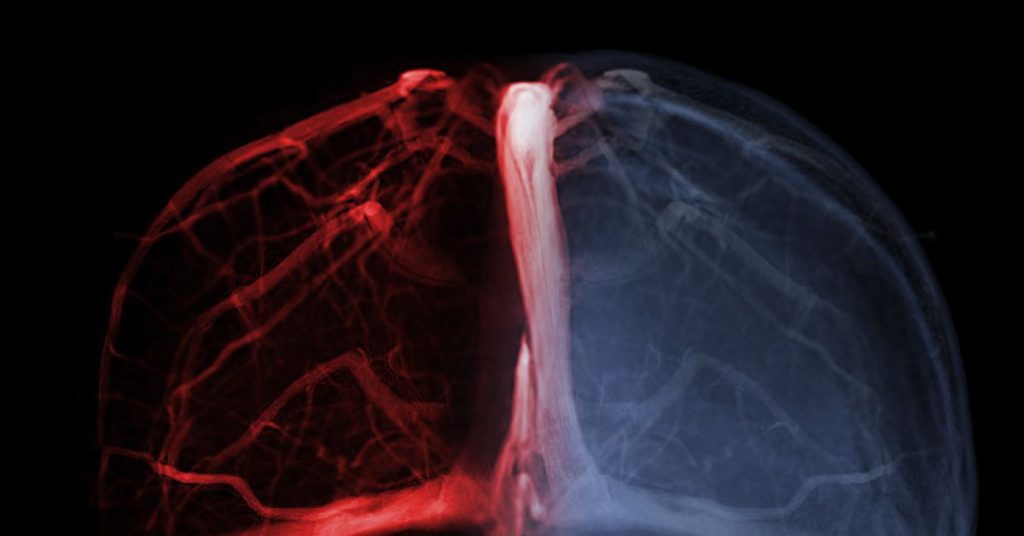

A trombose venosa cerebral (também chamada de trombose dos seios ou veias cerebrais) ocorre quando há formação de um coágulo sanguíneo nos seios venosos ou nas veias do cérebro, impedindo o fluxo normal de sangue e provocando aumento da pressão intracraniana, inchaço cerebral ou infarto venoso.

- Tomografia computadorizada com venografia (CTV) ou ressonância magnética com venografia (MRV) para visualizar os seios e veias cerebrais e identificar o trombo.

- A ressonância magnética convencional, associada à venografia por contraste, é considerada excelente para definir o diagnóstico.